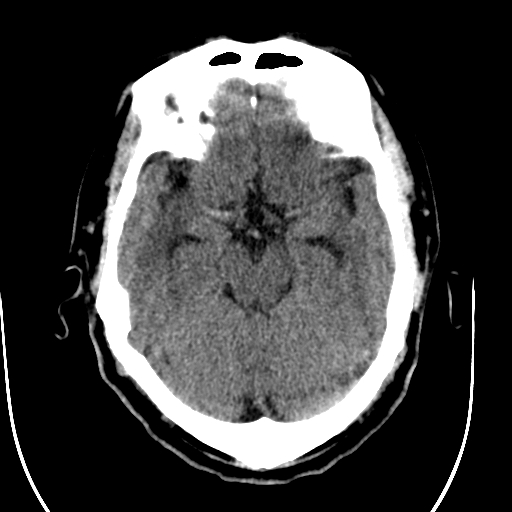

标题: CT28335:男,58岁,请各位看看是不是有脑积水,蝶窦内高密 [打印本页]

标题: CT28335:男,58岁,请各位看看是不是有脑积水,蝶窦内高密

脑积水!建议行mri!

1)脑积水。2)副鼻窦炎。